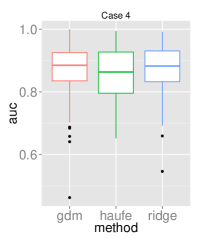

To assess the discriminative performance and reproducibility of the compared methods under varying confounding scenarios, we used the ADNI dataset. We simulated four distinct training scenarios in increasing potential for confounding effects: Case 1: AD + CN subjects, mean age balanced, Case 2: CN + AD, mean age balanced, Case 3: AD + CN, oldest ADs, youngest CNs, Case 4: CN + AD, oldest ADs, youngest CNs.

All models had their respective parameters () cross-validated in an inner fold before performing out-of-sample prediction on a left out test set consisting of equal numbers of AD and CN subjects with balanced mean age. Furthermore, the inner product of training model parameters was compared between folds to assess the reproducibility of models. Training and testing folds were shuffled 100 times to yield a distribution.

The prediction accuracies and the model reproducibility for the above cases are shown in figure 2. The results demonstrate that while GDM is not a purely discriminative model, its predictions outperformed ridge regression in all four cases. Regarding reproducibility, the Haufe et al. (2014) procedure yielded the most stable models since it yields a purely generative model. However, GDM was more reproducible than ridge regression.